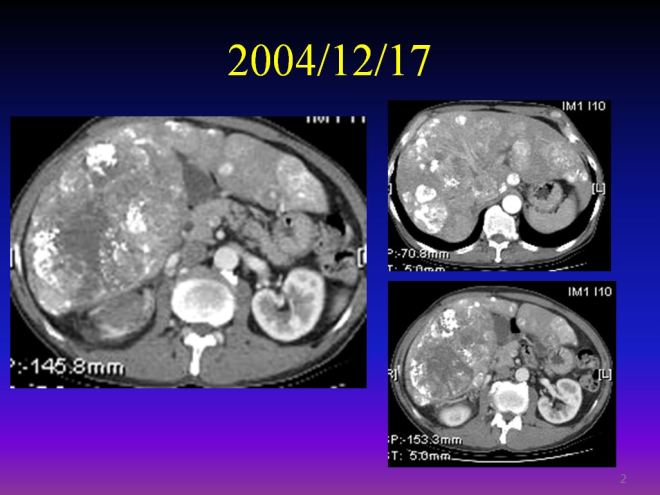

case : 말기 간암 간경화 색전술을 시술한 소음인 사례

이 환자 분은 2004년도 환자로서 내게 방문한 것은 2006년도이다. 환자가 치료 목적으로 온 것이 아니고 단지 체질을 알고 식이요법을 해 보고자 하여서 내원하였으므로 자료를 다 구비해 가지고 오지를 않고 CD만 몇 장을 가지고 왔다. 그래서 자세한 병력을 설명하지는 못한다. 이 환자의 당시 병력을 간단히 소개하면 B형 간염 보균자로서 활동성이 없다는 결과를 받고서 방심을 하면서 술 담배를 한 분이다. 20년 뒤인 2004년도에 간경화 말기와 간암 말기로 병원을 찾은 분이다.

이분은 소음인 체질로 당시에 내게 와서 식이요법을 알고자 하였다. 그런데 가지고 온 자료를 보니 너무 놀라웠다. 2004년도 색전술을 이미 시행한 당시 CT인데 자료를 소략하게 가지고 와서 내가 본 처음 자료만 수록하여 설명하겠다. 위에서 보듯이 간 전체에 다발적으로 (multiple) 암이 퍼져서 정상 간세포가 군데 군데 보이지 모두 암이라고 할 수 있다. 그리고 간도 경화로 위축이 되어서 간의 경계선이 모두 우둘두둘하다. 참고적으로 하얀 염색이 된 부분이 색전술을 시행한 다음에 항암과 리피오돌(lipiodol)이라는 접착제가 함께 들어가서 퍼져 있는 암세포의 부분이다. 한마디로 간 전체가 다 암이다. 그런데 이분이 2년 뒤인 2006년도에 나를 찾아왔다. 나는 어떻게 이 정도에서 2년을 견디었는가 궁금하였다. 그래서 병력을 물으니 간염을 1980년도에 발견하고 보균자인 것을 알았고, 후에 음성이라고 활동성이 없다고 하여서 평소대로 알코올을 즐기면서 살았다고 한다. 그리고 2004년도 간암을 발견했을 때는 너무 말기라 병원에서 치료를 거부 당하였다. 서울대에서 당시 한 보름 정도 살 것이라고 하였는데 삼성의료원을 찾아가서 또 진단하니 역시 같은 이야기를 하였다고 한다. 환자 생각에 그냥 죽기는 너무 억울하니까 색전술을 해달라고 졸랐다고 한다. 주치의는 색전술이 의미가 없다고 하였지만 환자 자신이 이를 해달라고 하였다. 보통 간에 점 한두 개에서 암이 발견되어서 색전술을 시행하여도 몇 달 뒤에 다시 재발하여서 무섭게 퍼지는 경우도 많은데 이분은 전체가 암일지라 색전술도 쉽지 않고 예후도 길지 않을 것이라는 게 일반적인 판단이다. 그런데 의외로 색전술이 이분에게 잘 반응을 하여서 2006년도까지 만 2년 넘게 생존을 하여서 나에게 찾아온 것이다.

다음은 색전술 1년 뒤인 2005년도 CT 사진이다.

간에 있던 암들이 현저히 소실이 되어서 암이 보이는 부분만 수록하였으므로 위와 level이 조금 다르다. 하지만 이전에 보이던 간 좌엽의 우들두들하던 경계면의 간이 약간 재생되어서 자라면서 매끈해졌고 리피오돌 uptake 된 부분이 현저히 줄어들었다. 다음은 2004년과 약 8개월 뒤인 2005년도의 비교 사진이다. 우리는 두 사진을 비교해 볼 때 색전술이 매우 잘 반응을 했음을 알 수 있다.